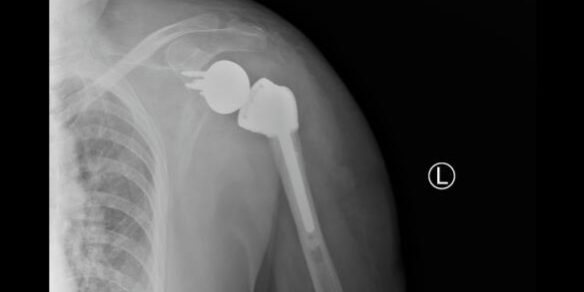

术后患者状况良好,第二天即可开始下地运动,肩枢纽也可以做一些简单的前后运动,X光片显示肩枢纽假体在位良好,目前患者已康复出院。

X光片显示肩枢纽假体在位良好